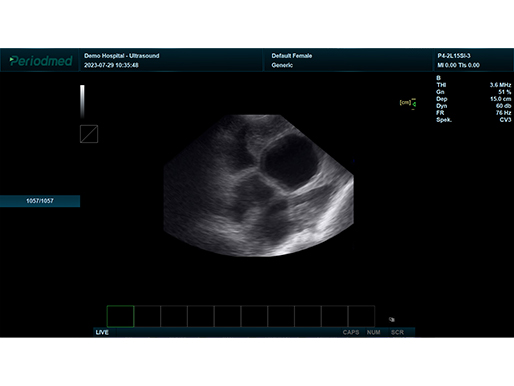

B模式 子宫 猪

B模式 子宫 猪

凸阵探头-B模式-子宫 猪

凸阵探头-B模式-子宫 猪